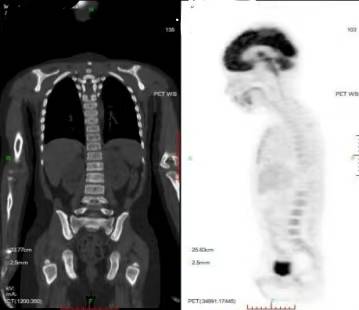

PET-CT(2022.5.12):

左侧眼眶后壁及左侧颞骨骨质破坏,伴颞面及左侧颞叶高密度影,代谢活性弥漫增高,有少量肿瘤代谢活性残余,评估为部分缓解(PR)。

PET-CT(2023.05.12):

颅骨、颞面及左侧颞叶高密度影消失。